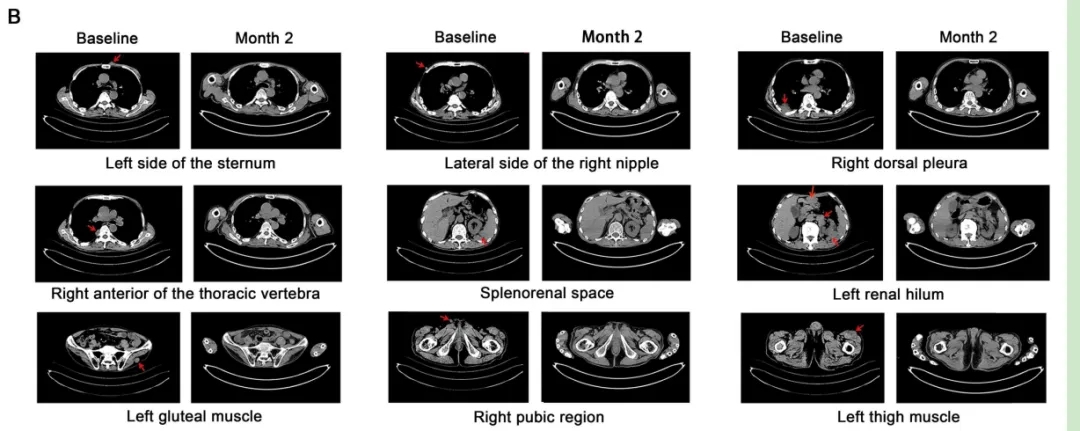

结果显示:接受ESO-T01治疗后,患者疗效显著。患者1在治疗第2个月达到严格意义上的完全缓解(CR),所有髓内和髓外病变均消退(详见下图B);患者2在第28天达到严格完全缓解,病变完全消退(详见下图D);患者3和4达到部分缓解(PR),至第28天肿瘤病变缩小,骨髓中微小残留病灶转阴。

▲图源“Lancet”,版权归原作者所有,如无意中侵犯了知识产权,请联系我们删除